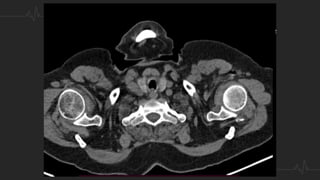

TÉCNICA - ANGIOTAC

• Contraste: 50 ml a un flujo de 4 ml/sg y lavado posterior con 30 ml de

suero salino

• Kilovoltaje se decide en función del peso del paciente: 80 kV hasta 70

Kg, 100 kV entre 70-100 Kg y 120 kV por encima de 100 Kg.

• Se dispara con un retardo de 6 seg, con técnica de bolus tracking,

posicionando el (ROI) en la arteria pulmonar, a 100 (UH).

• Adquisición se realiza con la respiración suspendida, pero no tras

inspiración profunda para evitar la dilución del contraste en la aurícula

derecha.

TÉCNICA - ANGIOTAC •Contraste: 50 ml a un flujo de 4 ml/sg y lavado posterior con 30 ml de suero salino • Kilovoltaje se decide en función del peso del paciente: 80 kV hasta 70 Kg, 100 kV entre 70-100 Kg y 120 kV por encima de 100 Kg. • Se dispara con un retardo de 6 seg, con técnica de bolus tracking, posicionando el (ROI) en la arteria pulmonar, a 100 (UH). • Adquisición se realiza con la respiración suspendida, pero no tras inspiración profunda para evitar la dilución del contraste en la aurícula derecha.